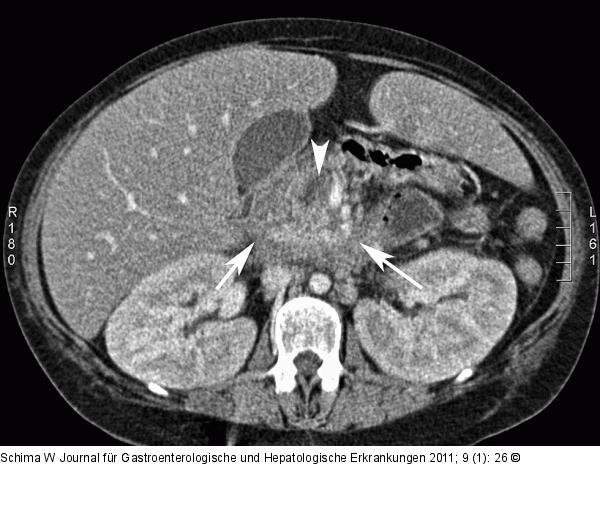

Abbildung 1b: Leberadenom Man erkennt eine Auftreibung des Pankreaskopfes (weiße Pfeile) mit einer umschriebenen Nekrose (Pfeilspitze). |

Man erkennt eine Auftreibung des Pankreaskopfes (weiße Pfeile) mit einer umschriebenen Nekrose (Pfeilspitze). |